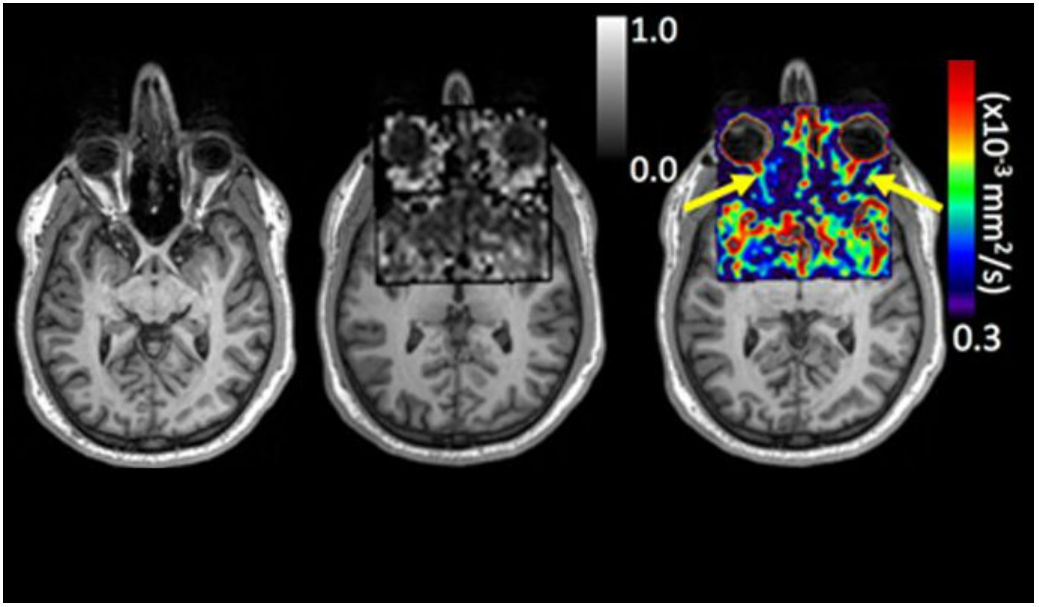

Addressing the Most Challenging Tissues in Magnetic Resonance

Popular science coverage of MRI challenges in difficult tissue environments and the broader translational impact of MR innovation.